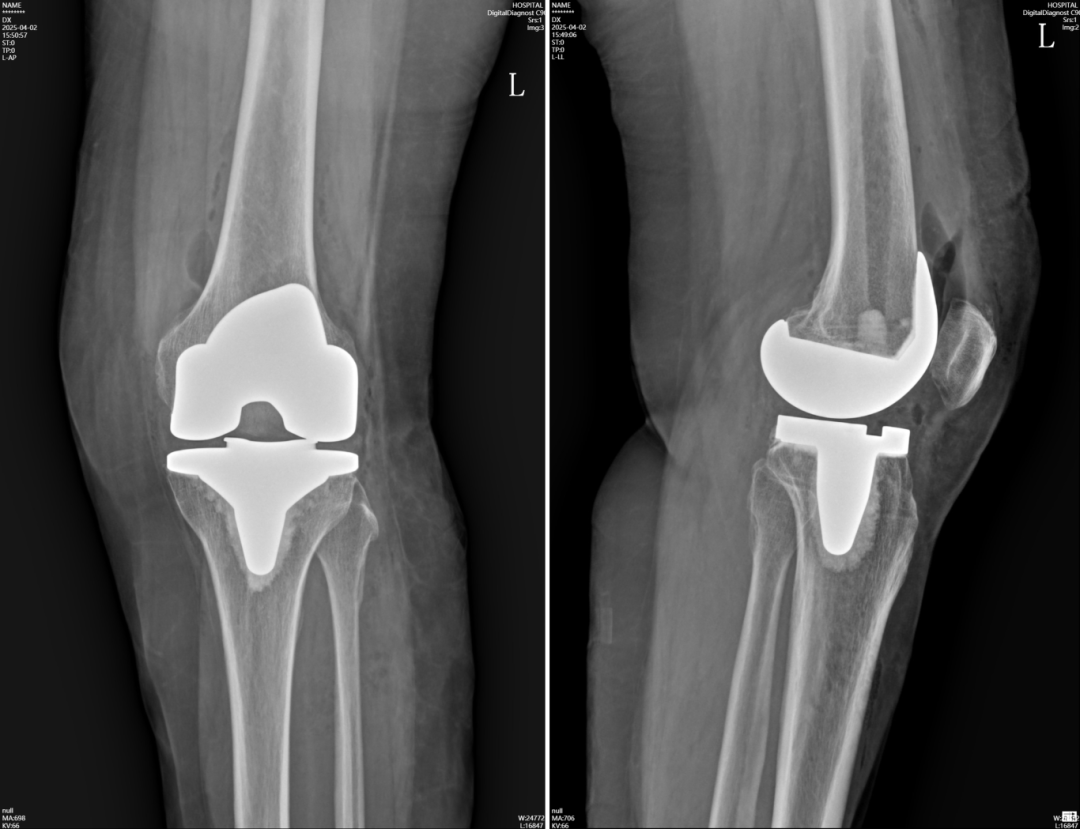

人工全膝关节置换术(TKA)是严重膝关节疾病的终末治疗手段,可改善膝关节功能,但需配合科学术后康复训练,否则易出现膝关节僵硬,无法达到手术应有的疗效,规律活动以恢复关节灵活性、肌肉力量及日常活动能力,是术后康复的关键。